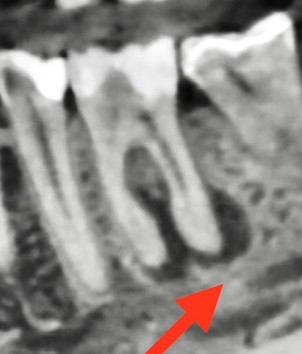

На снимке врач видит примерно такую картинку: чёрное облачко вокруг корня — это и есть периодонтит

Хронический апикальный периодонтит редко кто приходит лечить специально. Чаще всего его обнаруживают случайно: стоматолог делает рентген, а там — чёрное облачко вокруг корня зуба. Вот так он и выглядит.